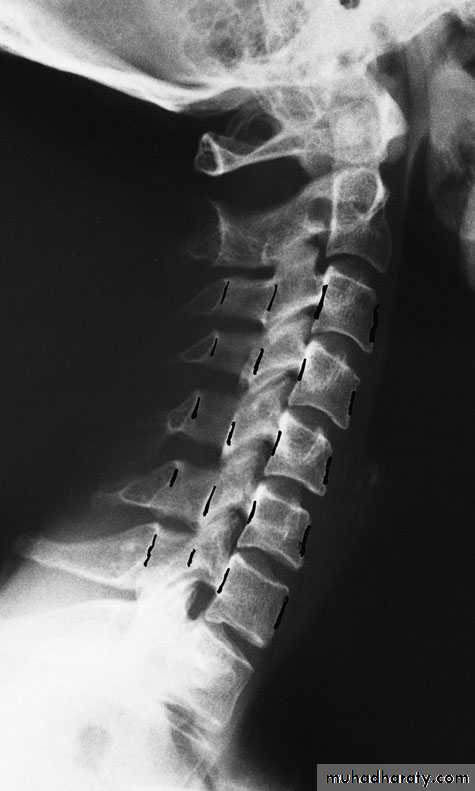

Cervical Spine X-RayLateral radiograph

A/P radiographThoracic Anatomy

Cervical Spine AnatomyNormal curvature is lordosis

Spinous Processes are BifidA flexible group of vertebrae that support the skull